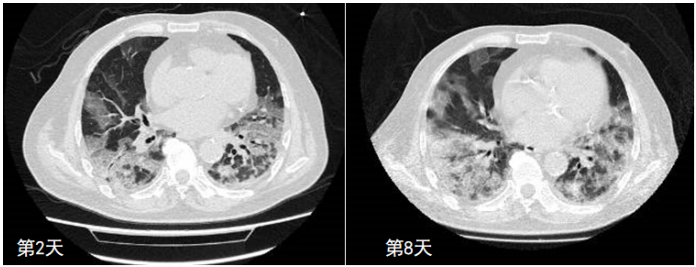

4. 关注早期气压伤征象—Macklin effect

前文提及的Macklin effect(PIE)预测患者出现纵隔气肿和皮下气肿是非常好的指标。如下图所示,在气管支气管束周围有明显的透亮带,即为PIE[26],一旦出现PIE,后续发生气胸或者纵隔气肿的情况明显增多。

图片

图源:Clin Imaging, 2023, 97:50-54.